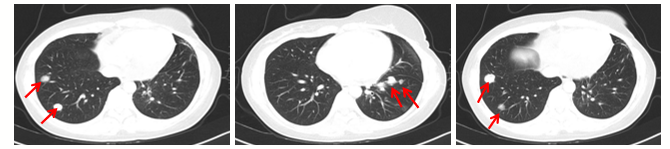

2018年9月(停药4月后),全胸CT检查显示双肺内多发结节影,最大1.2cm。

2018年9月至12月,患者于香港接受恩美曲妥珠单抗(T-DM1)治疗,疾病仍出现进展,PFS为3+月。2018年12月患者接受胸部CT检查显示双肺结节增多、增大,大者2.5cm。

图2 2018年12月,患者胸部CT检查结果